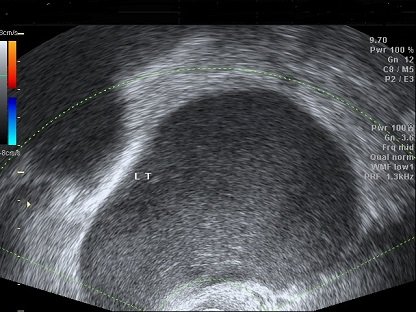

【111-1 醫學(六) 第45題】

一個30歲無性經驗女性來到門診,她主訴經痛已持續5年,長期使用止痛藥緩解症狀,此外她並無經血過多或頻尿之現象。她的經期剛結束,經安排婦科超音波檢查發現左側卵巢有一直徑約8x7公分的卵巢囊腫(如圖),下列何者為最可能的診斷?